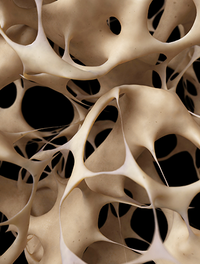

L’arsenal thérapeutique de l’ostéoporose s’est étoffé ces dernières années. Cependant, en dépit d’avancées majeures, aucun traitement [...]

Les fractures ostéoporotiques sont une cause majeure de morbidité et de dépenses de santé. Avec l’arrivée du denosumab (D) s’ouvre [...]